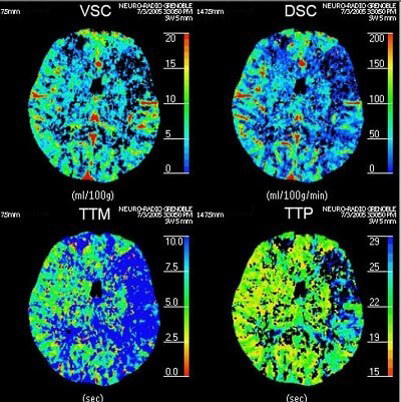

The instantaneous concentration of contrast material within each voxel is calculated by comparing the tissue attenuation at any time point with baseline images obtained before the arrival of the contrast bolus. Combining the measurements drawn from the several time points produces a concentration-versus-time curve (C1) for each voxel. Then a mathematical analysis of C1 for each voxel, generates a number of important parameters of hemodynamic performance, such as CBF, CBV, MTT, and the time-to-peak tissue response.

Now that we have a basic understanding of image acquisition in brain perfusion CT, we need to look at 4 essential hemodynamic parameters including: CBV, CBF, MTT and Tmax.